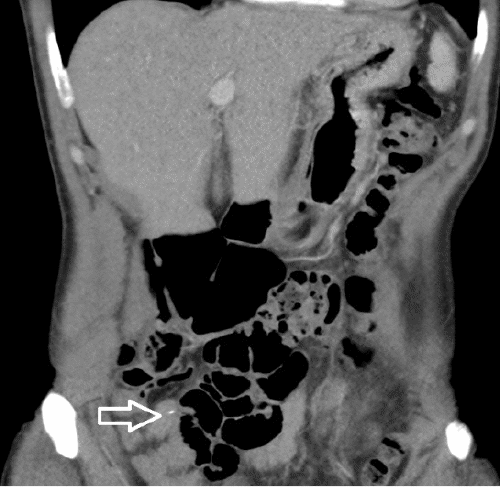

A 47-year-old female presented to the emergency department with a three-day history of waxing and waning right lower quadrant abdominal pain after eating a hamburger cooked on a home grill. She was afebrile, hemodynamically stable, with a white blood cell count of 5400 cells/ml. The patient had no evidence of peritonitis or free air, and a perforation was not suspected. CT imaging of the abdomen and pelvis demonstrated a metallic foreign body in the terminal ileum, without abscess or free air to suggest perforation (Figure 1).

Figure 1. CT Scan of Abdomen and Pelvis Depicting Metallic Foreign Body. Published with Permission

A) Terminal ileum, axial view

B) coronal view